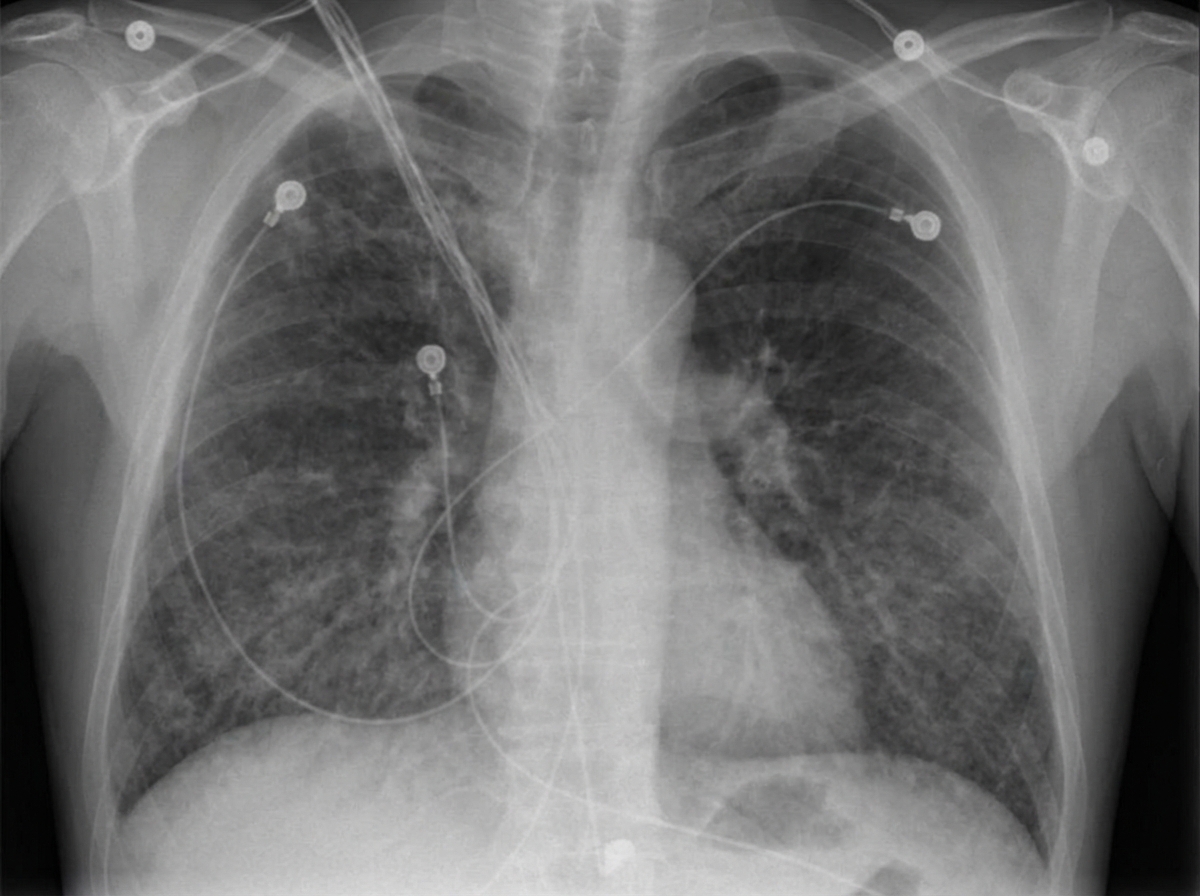

Four days after undergoing a Whipple procedure for newly-diagnosed pancreatic cancer, a 65-year-old man has shortness of breath. His surgery was complicated by bleeding for which he required intraoperative transfusion with 4 units of packed red blood cells and 1 unit of platelets. His temperature is 38.8°C (101.8°F), pulse is 110/min, respirations are 26/min, and blood pressure is 95/55 mm Hg. Pulse oximetry on room air shows an oxygen saturation of 85%. Cardiac examination shows normal heart sounds and no jugular venous distention. Auscultation of the lungs shows diffuse crackles bilaterally. The extremities are warm and there is no edema. Laboratory studies show a leukocyte count of 17,000/mm3 and hemoglobin concentration of 9.8 g/dL. Arterial blood gas on room air shows: pH 7.35 PaO2 41 mm Hg PaCO2 38 mm Hg HCO3- 25 mEq/L The patient is intubated and mechanical ventilation is initiated. An x-ray of the chest is shown. Transthoracic echocardiography shows a normally contracting left ventricle. Which of the following is the most likely cause of this patient's current condition?